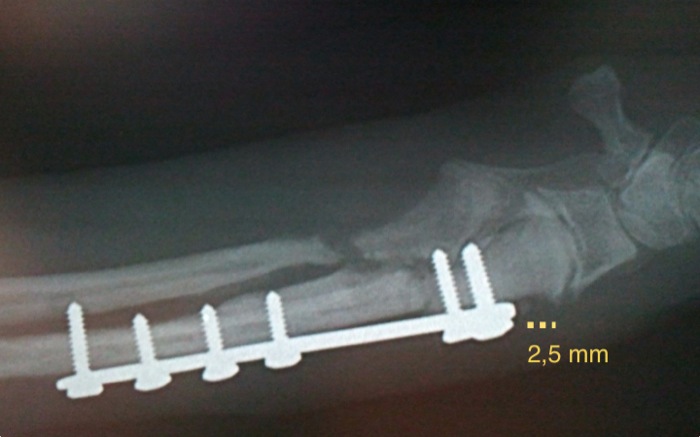

La fractura está desplazada y cerca de las lineas de crecimiento. El espacio distal de trabajo en el radio es de menos de un centímetro y debemos respetar un espacio tanto del foco de fractura como de la fisis distal.

La placa en T permite en 7 mm colocar los 3 tornillos distales de 2 mm. Cuatro tornillos se colocan en el fragmento proximal. Se tiene cuidado especial en no tocar la fisis del radio dado el gran potencial de crecimiento a esta edad de 4 meses a parte de quedar fuera del foco de fractura.

A las 2 semanas se realiza una placa control y aunque las fracturas evolucionan adecuadamente la fisis cubital presenta indicios de cierre prematuro. En el radio (que ha crecido 2,5 mm) hay formación de cayo óseo evidente y si el cúbito tarda suficiente en soldar evitaremos un valgus. Este punto no se cumplirá y tendremos un cúbito que ejercerá de cuerda de arco y hará de freno lateral al crecimiento del radio. Al mes de esta radiografía se recomienda operar pero el propietario decide esperar.